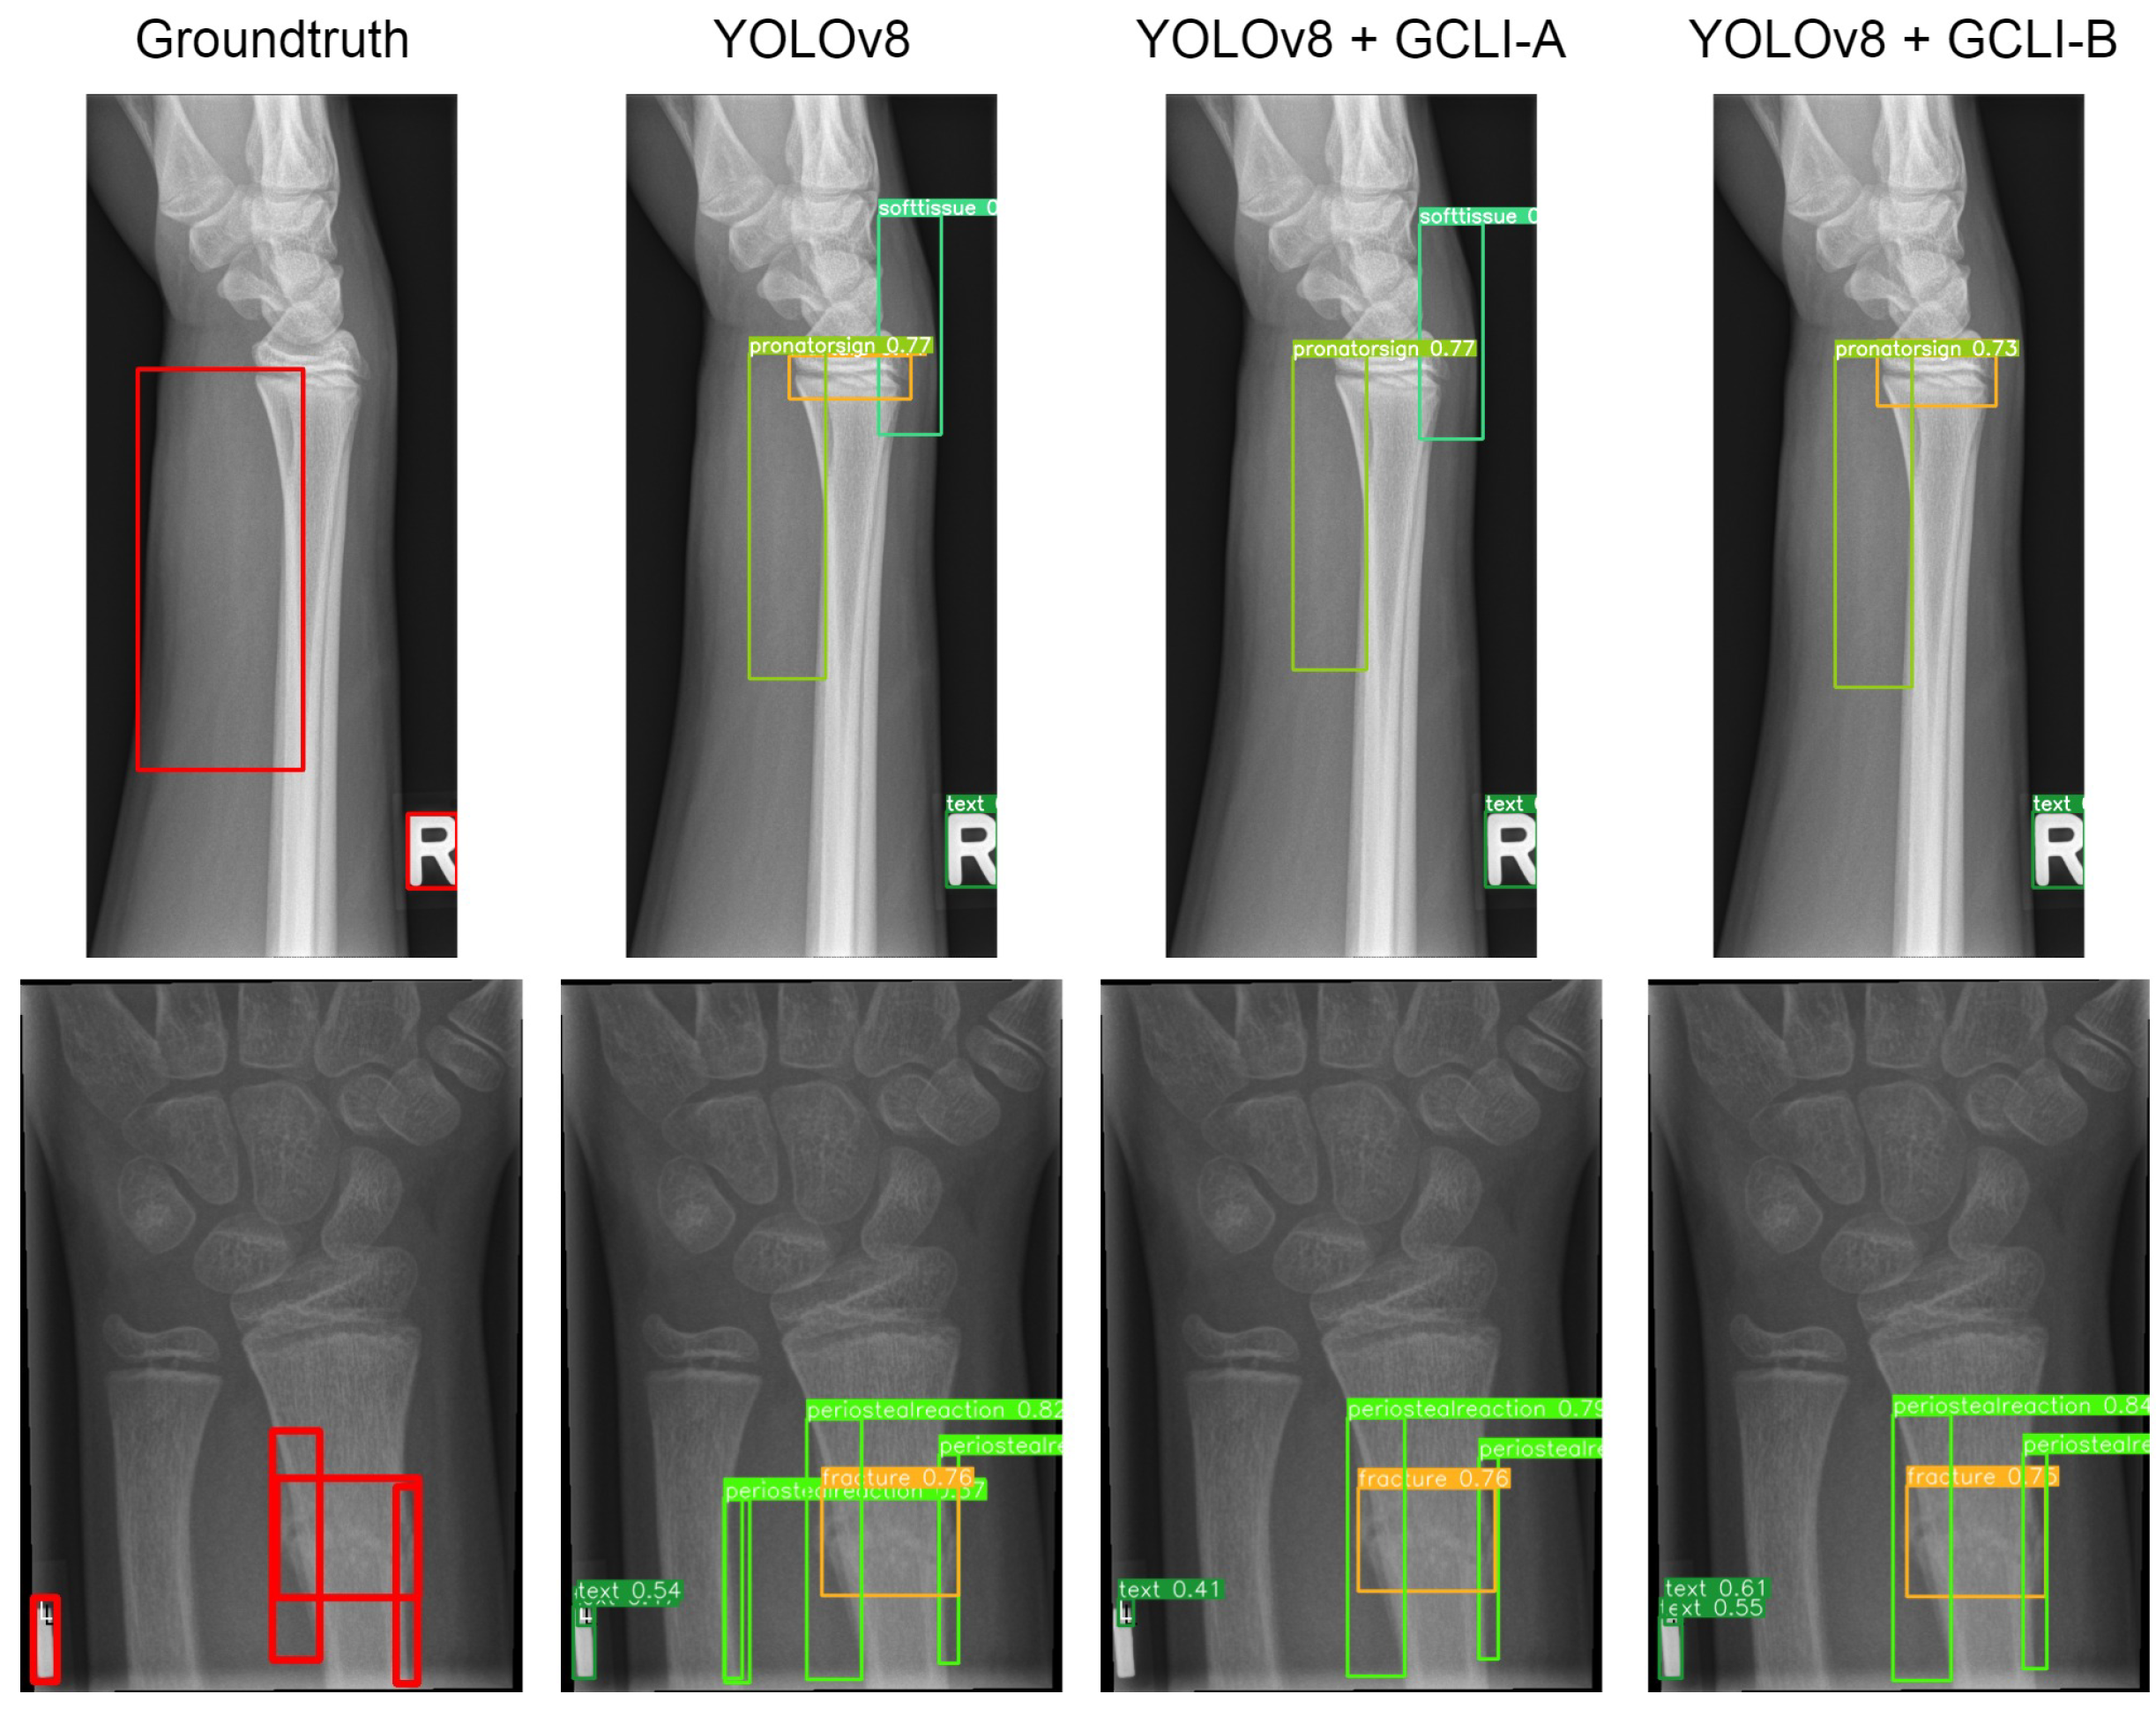

Next is another object detection task with the large-scale GRAZPEDWRI-DX dataset. Table 10 illustrates the performance of RT-DETR and YOLOv8 with attention modules on the GRAZPEDWRI-DX dataset. The attention modules are fused in the ResNet50 as the backbone for the extraction phase of RT-DETR and at the end of every scale in the aggregation phase of YOLOv8. However, due to the extremely high computation cost of simAM in RT-DETR, the experiment cannot be conducted on time. Therefore, there are no reported data of simAM in this term.

As Table 10 illustrates, some attention modules when fused with DL models tend to worsen the overall performance, such as ECA, CA, CBAM, and even GC block. In terms of RT-DETR, the DL model with the GC block attached maintains the same mAP50 as the baseline model, whereas the other ECA and CA only assist the model in reaching 42.1% and 41.8% mAP50, respectively. In terms of YOLOv8, both models with ECA and CBAM attached only achieve 48.6% and 48.9% mAP50, respectively. Even with simAM attached, the mAP50 of YOLOv8 is only sightly improved from 49.1% to 49.5%. These figures indicate that previous attention modules are struggling with noisy labels on medical images; while some tend to bring marginal improvement to the DL models, others may deteriorate the feature maps, resulting in a decrease in performance. On the other hand, our proposed GCLI modules effectively address this problem. For instance, GCLI module A enables the RT-DETR to reach the highest figure in mAP50, which is 43.9%, while GCLI module B assists the model in reaching the highest recall, which is 45.7% without adding many extra parameters. Moreover, in terms of YOLOv8, GCLI module B allows the model to reach the highest performance of all categories, which are 52.1% mAP50 and up to 32.5% mAP50-95. From Table 9 and Table 10, it is obvious that GCLI module A performs better than GCLI module B in RT-DETR architecture, and GCLI module B outperforms GCLI module A in the YOLOv8. The findings show that the GCLI modules add weighted redundancies more during the aggregation phases than the extraction phases. The partial attention strategy can effectively lessen the impact of weighted redundant features. Based on our observations of how two different GCLI modules behave, we can conclude that local interaction can greatly enhance the performance of global context modeling, outperforming bottleneck structures in assisting the DL model with noisy labels. Moreover, the experiments also indicate that the partial attention strategy can play a vital role in addressing noisy labels on many medical image datasets. In order to fully utilize the performance of GCLI module B, it is crucial to consider placing the attention module at the later phases of the architecture, while the extraction phases may be more suitable for GCLI module A. Figure 16 and Figure 17 show how well our GCLI modules address the noisy labels compared to baseline models. It can be seen that the proposed GCLI modules can guide the model to the more potential lesion areas, significantly providing less redundant predictions, especially in the case of GCLI module B. The results indicate that our GCLI modules can be a suitable option for improving model performance with a small trade-off in complexity to gain a better detection ability in the scenario of noisy labels of several medical imaging datasets.